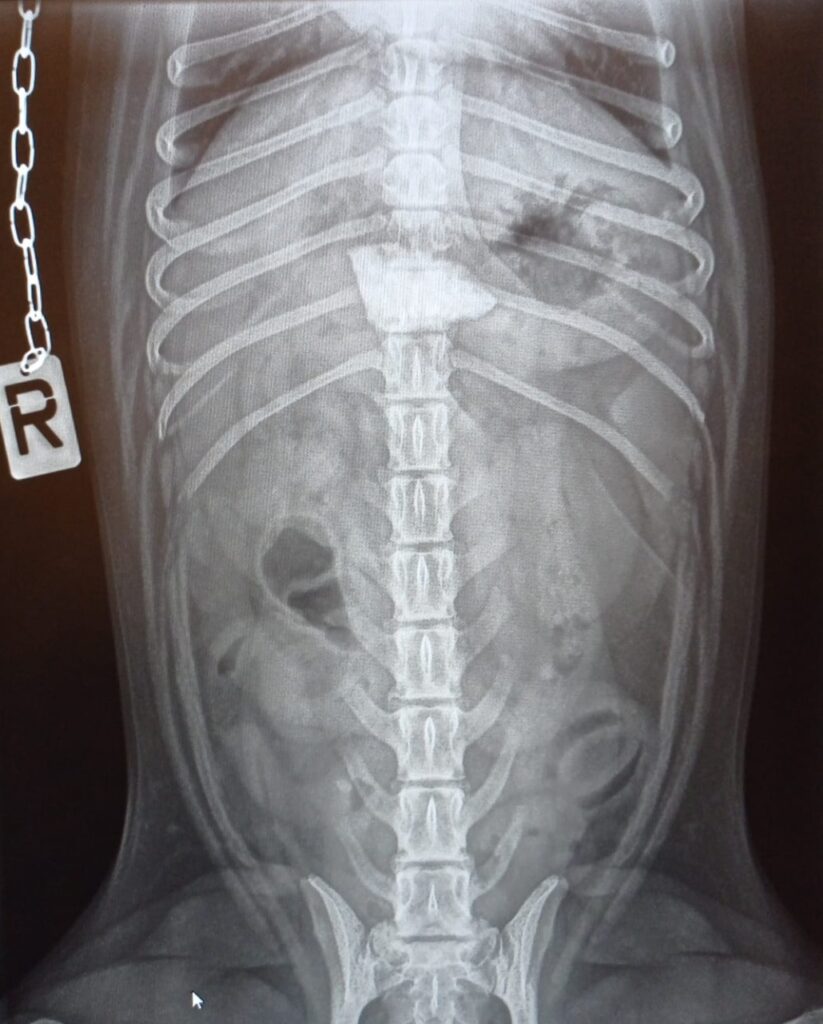

Ester päätettiin rauhoittaa kevyesti röntgenkuvantamista varten. Rauhoituksessa Esteriltä otettiin 3 röntgenkuvaa vatsaontelosta useasta eri suunnasta, näissä näkyy mineraalitiheä ja teräväreunainen vierasesine vatsalaukun alueella (susp. kivi). Koska kivi oli suhteellisen suuri Esterin kokoon nähden, päädyttiin, että kiven leikkauksellinen poisto on suositeltavaa. Kivi ei sula ruoansulatuskanavassa ja voi aiheuttaa suolistossa suolitukoksen. Teräväreuneinen kivi voi myös vahingoittaa suolen seinämää ja pahimmillaan puhkaista sen. Suuren, teräväreunaisen vierasesineen oksennuttaminen ei myöskään ole turvallista, koska vierasesine voi jäädä jumiin ruokatorveen tai vahingoittaa ruokatorvea.